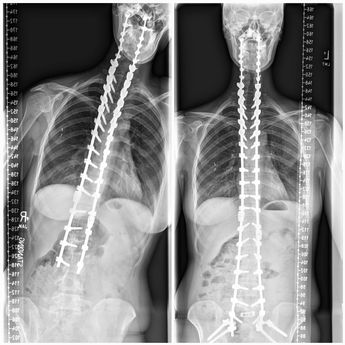

Megan King was reportedly pictured recently after one of her many surgeries. She is believed to not be able to twist or bend her spine in any direction and the same goes for her head. So as you can imagine, life is pretty tough for her.

The injury may have taken place in the year 2005 but today, the 33-year-old can’t move, twist, or bend in any direction.